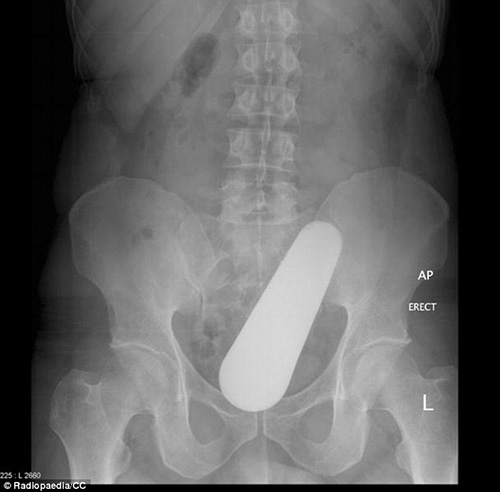

VBF- Đây là các hình ảnh được cung câp bởi các bã sĩ trong bệnh viện. Các bênh nhân sau khi để lọt các đồ vật vào người đã phải đi cấp cứu tại bệnh viện và đã được chụp X-quang để xác định đồ vật đó.Đó thường là những "vật dụng bất bình thường" được các bác sĩ khắp thế giới tìm thấy bên trong trực tràng của các bệnh nhân và chia sẻ trên trang Radiopaedia, một website giáo dục và thảo luận do các sinh viên X-quang thành lập từ năm 2005. Hình ảnh X-quang được chia sẻ trên website là vật mẫu cho việc nghiên cứu hợp tác và là giáo cụ trực quan trong giảng dạy ngành học quang quyến (môn học X-quang), hoặc dùng làm tài liệu cho các bảo tàng, đồng thời là những ví dụ giúp mọi người cảnh giác. hiếc chày trong trực tràng người đàn ông 40 tuổi được "khổ chủ" giải thích khi nấu món ăn Malaysia đã bị trượt vào trong??? Một chai đựng cà phê với những chiếc ghim gắm vào lớp cao su phía dưới nắp được bệnh nhân đưa vào trong cơ thể. Một tuýp đựng vitamin được đưa vào trong trực tràng. Thậm chí một chiếc chai cũng nằm trong danh sách bộ sưu tập các bác sĩ X-quang thu thập được. Dụng cụ rung được đưa vào qua đường hậu môn. tm tm